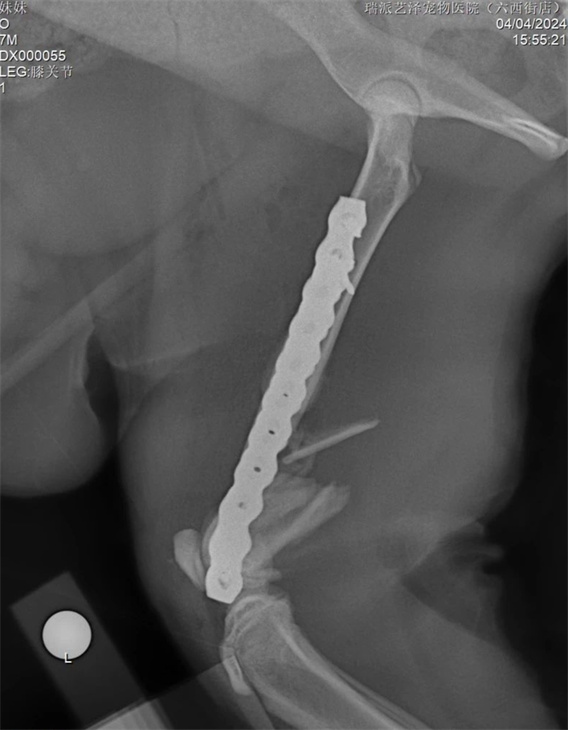

意外事故時有發生,導致各種災難性的後果。有時我們可以救治,但很多時候我們卻無能為力。這隻貓從高處跳下,遭受了嚴重的粉碎性骨折。手術的困難在於:幼貓需要考慮股骨的生長問題。幸運的是,6個月以上年齡的貓,股骨遠端生長板已經沒有太多剩餘的生長空間。其次,也要考慮動物術後無法有效限制運動,這涉及到股骨遠端髕股滑車和膝關節的活動。所採用的固定結構要考慮生長、機械穩定性和骨癒合等因素。基於上述考慮,股骨遠端採用內外雙板固定,既穩定又能中和骨骼的軸向壓縮力。 PRCL-6.5+5mm 骨板 內外固定採用股骨乾螺絲固定。採用膝關節外側入路,延伸至股骨中部。先行股骨內側固定,內側骨板不需過多塑形,再進行外側固定。在結構和力學穩定的情況下,盡量少用螺絲,盡量採用鎖定螺絲固定。術後需加強活動,避免肌肉沾黏及股四頭肌收縮。術後可使用預防性90-90繃帶固定3-5天。

手術後追蹤及複查一切正常。